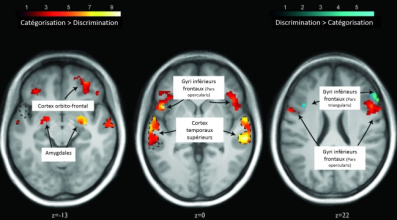

Comment notre cerveau décode le regard de l'autre

Notre attention captivée par un regard

Voix et émotions : la clé est dans le front